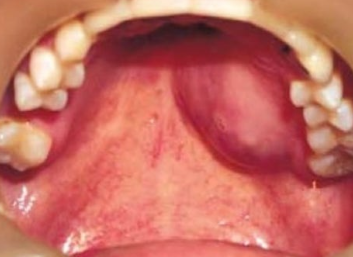

침샘암의 가장 대표적인 초기 증상은 통증이 없는 몽우리가 침샘 부위에 만져지는 것입니다. 이는 많은 사람들이 놓치기 쉬운 신호입니다. 통증이 없기 때문에 대수롭지 않게 여기거나 단순한 염증으로 오해하기 쉽기 때문입니다.

침샘에 발생된 종양은 대부분 서서히 자라며, 귀밑 몽우리나 턱 밑, 혀밑 등에 덩어리로 나타납니다. 손으로 만졌을 때 움직이고 혹처럼 만져진다는 특징이 있으며, 얼굴이나 목 부위에 덩어리가 만져져서 병원을 찾는 경우가 일반적입니다.

소타액선 암의 경우

- 코막힘

- 코피

- 시야 장애